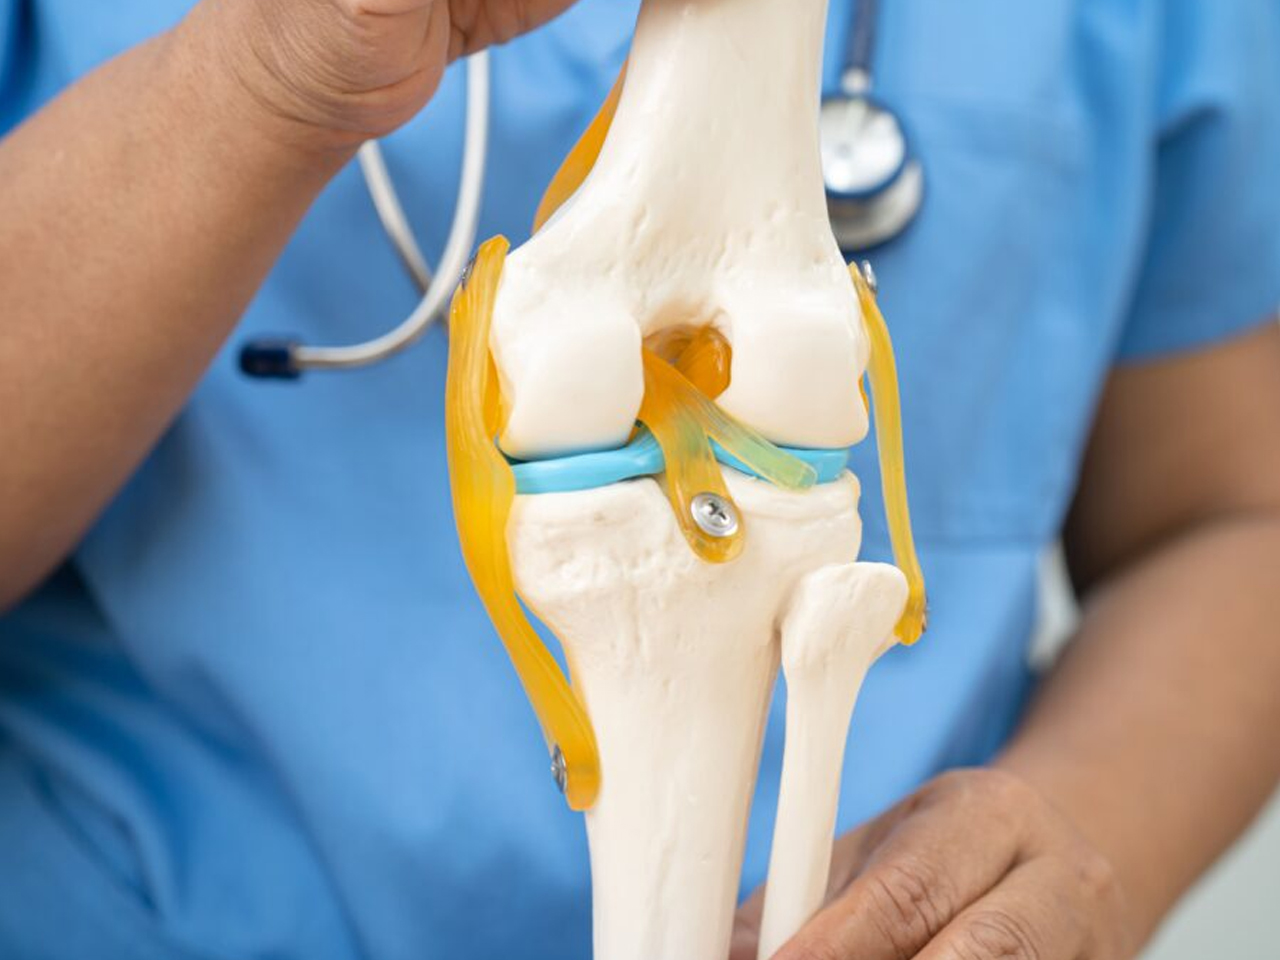

Partial knee replacement (PKR) is also called unicompartmental knee replacement because in this surgical procedure only the damaged portion of the knee joint is replaced with an artificial implant.

The following tissues are preserved in this joint replacement procedure:

The objective is to preserve natural knee joint tissue as much as possible. Therefore, only a few components are used.